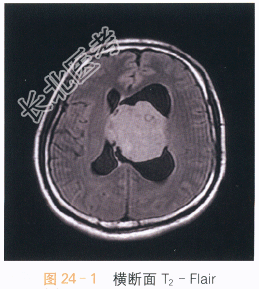

影像学资料如图24-1~图24-4所示。

读片分析:头颅MRI检查横断面T₂-Flair可见左侧侧脑室及透明隔区不规则软组织肿块,呈等高信号影,病灶内可见小片状囊变影,左侧侧脑室扩大,右侧侧脑室受压;增强扫描可见片状不均匀明显强化,囊变区无明显强化。结合患者病史,可考虑诊断为中央神经细胞瘤。